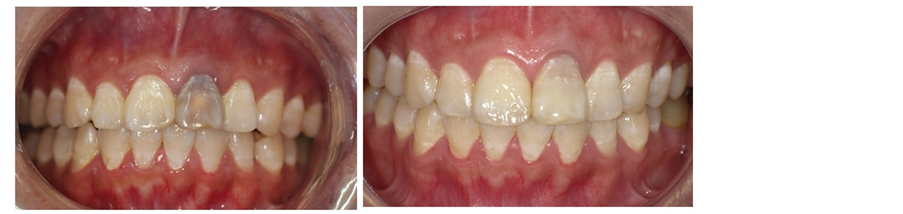

mm (Figures 4-6). 3) Scratch the apex and wash it with normal saline. Restore and suture the mandibular with minocycline smeared in partial (Figure 7). 4) Post-operative CBCT shows that root filling was improved and the resistant projection of agglomerate at apex disappeared (Figures 8-9). 5) Fistula disappeared 1 week after operation (Figure 10). 6) Intracoronal bleaching was conducted and then medical prescription was changed twice in follow-up visit. The color of 21st tooth became 11 and 12 with resin repair at the incisal margin of 21st tooth. 7) The color change of bleaching opisthosoma is relatively obvious than that in neck. The color of tooth neck is dark. The protective screen was established for the third bleaching. Four days later, further consultation was conducted with color of tooth neck improved. The patient was satisfied (Figure 11). 8) 1, 3, 6 and 12 months after operation, further consultation was conducted in follow-up (Figure 12).

Figure 11. Bleaching effect four times.

Figure 12. Follow-up at 3, 6, 12 months after surgery.

Figure 13. Pre-operation and post-operation.